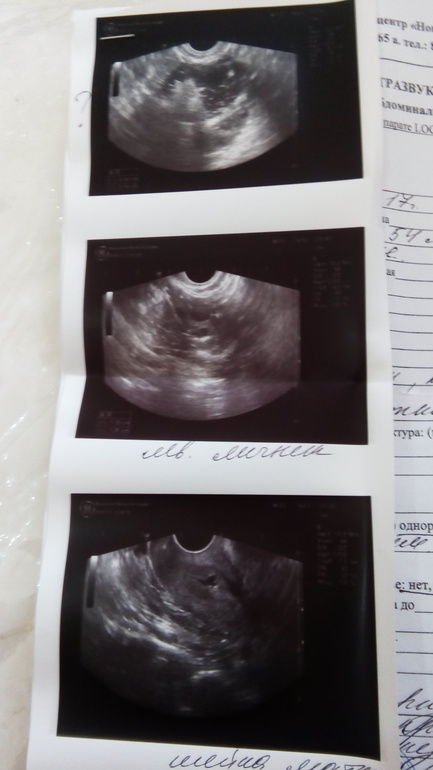

Меня отправляют на МРТ, на онкомаркер,и потом га лапару.Отправляют по причине кисты

Спасибо,а то гинекологии на УЗИ не видят нечего,не находят яичник,находят уплотнение высоко,где уже кишечник. Сегодня 45 минут ковяряли меня,разными датчиками,руками.Беременность не наступит,без операции?Доминантный есть фоликул,12 мм.в левом яичнике